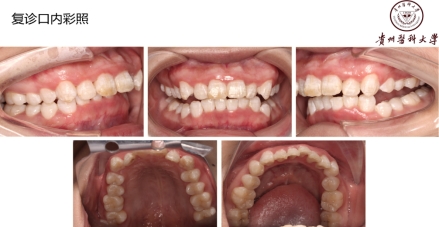

治疗以及预后:排除了白血病、艾滋等严重疾病,明确诊断后,病人也不要过分担心。这种病发病急,治疗效果及预后也好。治疗时去除牙石及坏死组织,局部止血,双氧水充分冲洗,口服抗厌氧菌药物替硝唑等,全身支持治疗:高蛋白饮食、维生素C等。一定要改变生活习惯,避免熬夜,戒烟,放松心情,保持口腔卫生!

定期牙周检查:最后,大家半年到一年就要定期来专业的口腔医院进行口腔检查!尤其是牙周的检查哦!!对于口腔的疾病要早发现、早治疗,只有这样,治疗才会越简单、费用也会越低!!!